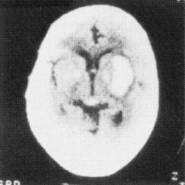

A 73-year-old man has been experiencing increasing drowsiness and incoherence. He has a history of arrhythmias and has fallen twice in the past 2 weeks. There are no focal deficits on neurologic examination. Acontrast CT scan of the head is shown in the figure below. Which of the following is the treatment of choice?

The CT scan shown in Figure demonstrates a smooth, biconvex lens-shaped mass in the periphery of the right temporoparietal region. This picture is characteristic of a subdural hematoma that is a result of laceration of veins bridging the subdural space. Unlike an epidural hematoma, which expands quickly and progresses rapidly to coma, a subdural hematoma is initially limited in size by increased intracranial pressure and expands slowly. Symptoms may follow the inciting trauma by several weeks. Altered mental status is often more prominent than focal signs and may progress from confusion to stupor to coma.

Treatment consists of evacuation of the clot via burr holes. Antibiotics and antifungal agents have no role, and fibrinolytic therapy or delay in treatment could be harmful.